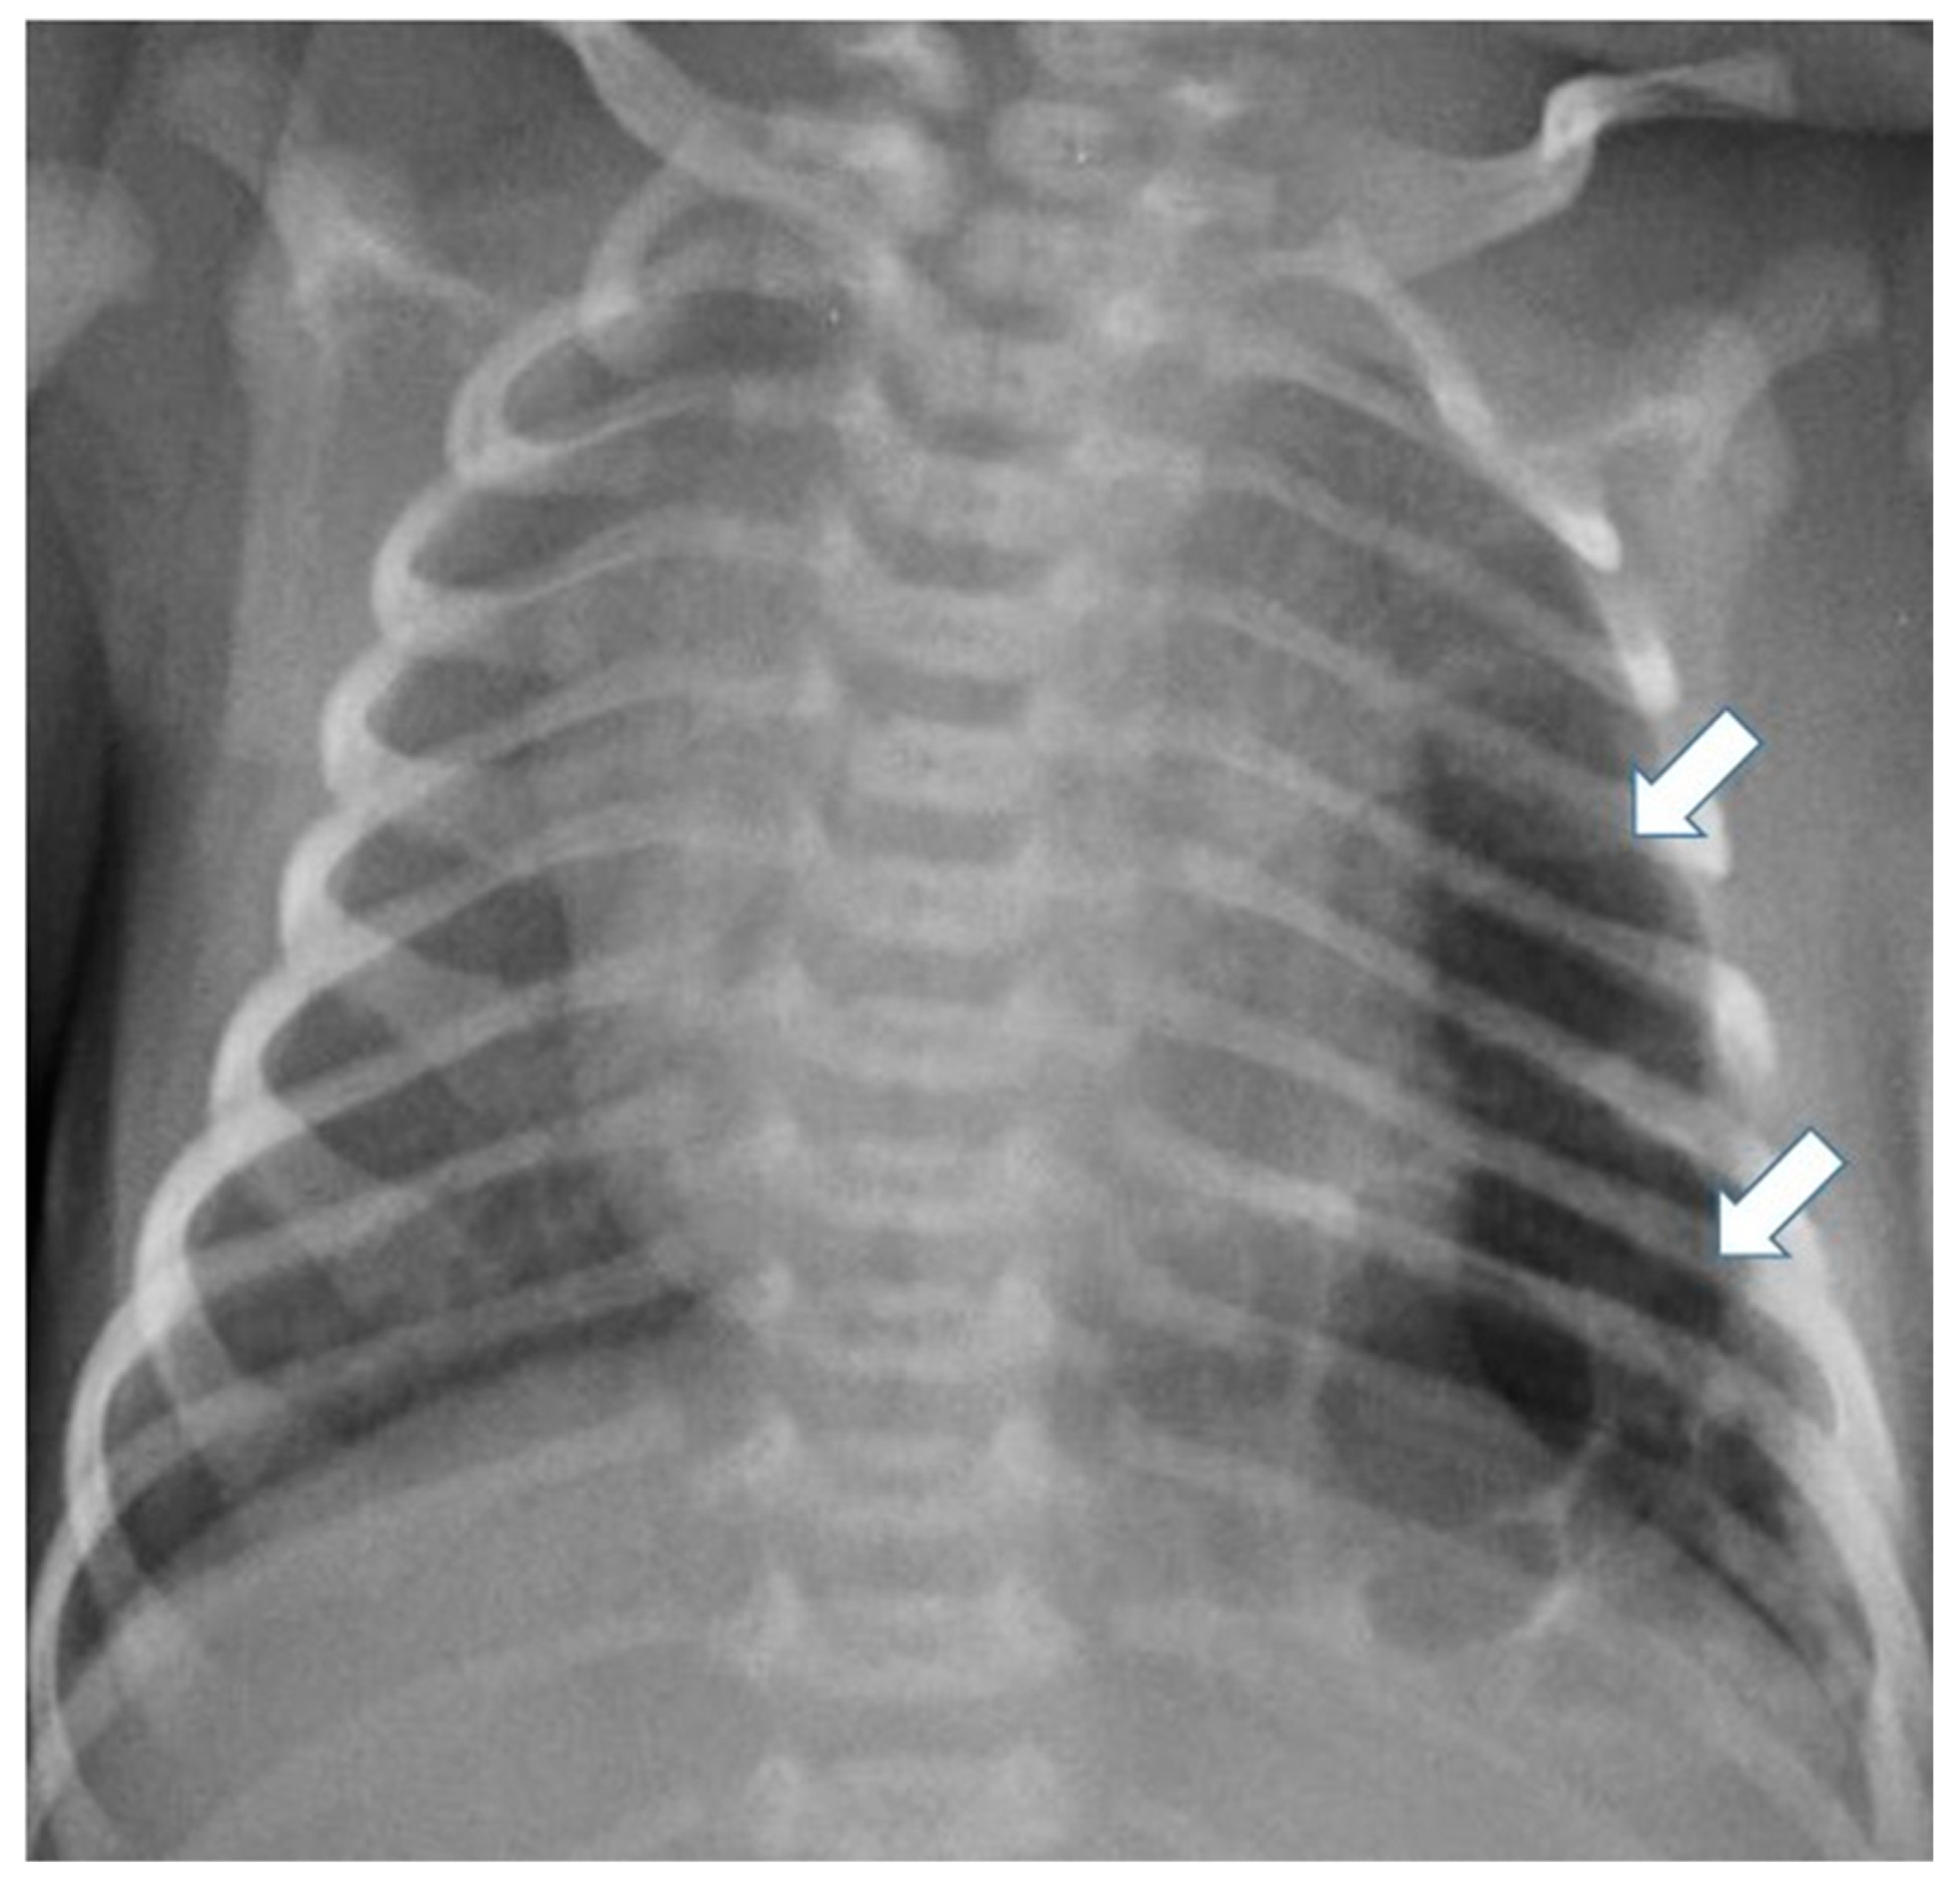

Postnatal chest radiography shows a region of variable opacity, dependent on the solid component of the lesion and the fluid contents of the cysts; a mediastinal shift may be associated [3,8] (Figure 3 and Figure 4).

Figure 3.

Chest radiograph of a newborn shows multiple large air-filled cysts in the left lower lobe (arrows), suggesting a type 1 CPAM.

CT allows for the better evaluation of the lesion and its relationships with adjacent structures. On CT scans, lesions are detectable as well-defined air-filled spaces variable in size depending on CPAM type [15]: type 1 CPAM appears on CT as a one or multiple large cystic structures which can be entirely filled with air or with air-fluid levels (Figure 3, Figure 5 and Figure 6); type 2 CPAMs are visualized on CT as air-filled multicystic masses or focal or ill-defined areas of consolidation [3,15] (Figure 4 and Figure 7); type 3 typically exhibits a solid appearance on CT [15]. In infected CPAMs, imaging can demonstrate internal air-fluid levels and an enhanced thick wall.